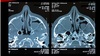

39

Dx

Sinusitis

40

Mucocele con papiloma nasal invertido el que esta hiperintenso El que esta hipointenso probable polipo o tumor | es RM T2